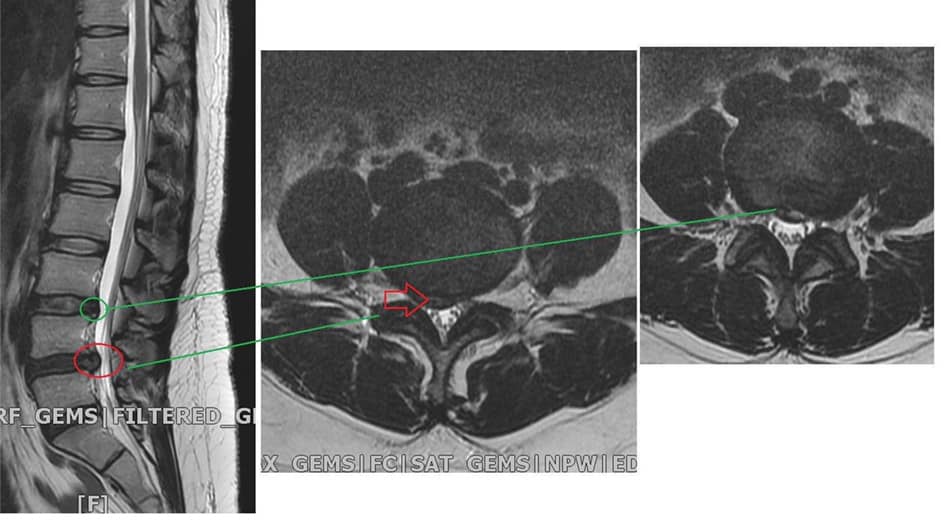

Cervical Spine Treatment Cases 腰椎治療案例 #今天來聊巨大骨刺為何可以吸收回去! #椎間盤突出需要多久才能吸收呢? #馬尾神經症候... 2020.09.08 #典型假性坐骨神經痛 #原來是梨狀肌症候群 #核磁共振排除椎間盤突出 #抽絲剝繭真相大... 2020.08.13 #嚴重椎管狹窄醫案 #感謝台北林大哥熱情見證 #從寸步難行到輕快漫步 #鍛鍊多裂肌的重... 2020.08.12 #椎間盤突出可以吸收回去嗎 #微針治療原理是什麼 #何時一定要接受神外開刀 #一張圖秒... 2020.08.11 #感謝花蓮鄉親林大姐熱情見證 #一分鐘認識椎管狹窄 #原本痛到無法走路打算開刀了 #脊... 2020.08.01 #感謝新莊區林先生熱情見證 #椎間盤突出跟纖維環裂隙的關係 #纖維環破裂突出可以不... 2020.07.28 #逆轉勝又一發case #原本疼痛一年多想說一定要手術治療了 #八週治療後症狀全部消失 #... 2020.07.25 #巨大椎間盤突出一定要開刀嗎 #除了開刀以外的選擇 #感謝台北市吳先生熱情見證 2020.07.24 #腰椎滑脫的疼痛心酸誰人知啊 #一分鐘瞭解腰椎滑脫 #哪一種情況需要積極開刀 #要如何... 2020.07.21 #巨大椎間盤脫垂一定要開刀嗎? #感謝新店林先生熱情見證受訪 #西醫手術有那些選擇... 2020.07.02 #纖維環裂隙AnnularFssures #MRI看起來不嚴重卻嚴重困擾患者 #感謝桃園市蕭先生熱情見... 2020.06.19 #骨刺有可能吸收回去嗎?? #疼痛超過六年的特殊案例探討 #MRI核磁共振前後對比 #感謝... 2020.06.14 #坐骨神經痛一定要開刀嗎 #突出的骨刺真的可以自己吸收嗎 #最新英國醫學期刊BMJ的看... 2020.05.30 #骨刺跟突出髓核有可能吸收回去嗎?? #特殊案例探討 #核磁共振一年後對比 2020.05.29 #從醫以來第一次碰到薦椎Tarlov cyst囊腫#左邊紅色圈圈是個案,右邊是國外案例#腰... 2020.05.23 ← 上一頁 10 11 12 13 14 下一頁 →